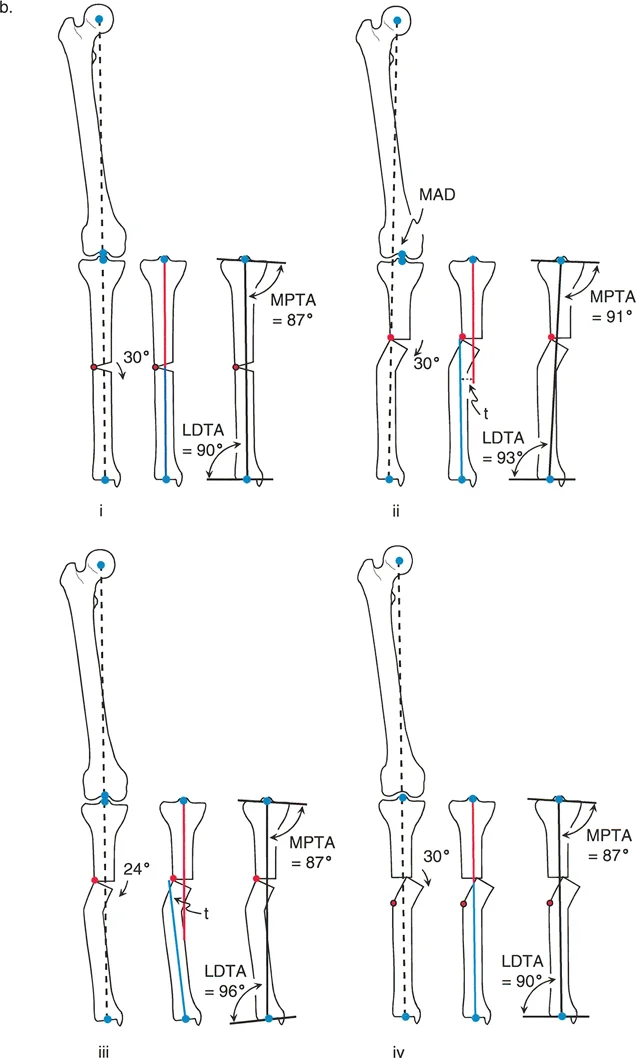

إن نجاح جراحة تصحيح تشوهات الأطراف يعتمد بشكل كبير على التخطيط المسبق الدقيق. هذا التخطيط أشبه برسم خارطة طريق هندسية تضمن أن كل خطوة جراحية تقود إلى النتيجة المرجوة. يعتمد هذا التخطيط على "مبادئ بالي" التي تحدد ثلاثة متغيرات هندسية أساسية في كل حالة:

- مركز دوران التشوه (CORA - Center of Rotation of Angulation): هذه هي النقطة المحورية للتشوه في العظم. يحددها الجراح من خلال رسم محاور الطرف قبل الجراحة.

- محور تصحيح الزاوية (ACA - Angulation Correction Axis): هذه هي النقطة التي يدور حولها الجزء البعيد من العظم لتصحيح التشوه. يتحكم الجراح في هذه النقطة عن طريق وضع المفصلات على المثبت الخارجي أو نقطة الارتكاز للوحة التثبيت.

- مستوى قطع العظم (Osteotomy Level): هذا هو الموقع الفعلي الذي يتم فيه قطع العظم. يتحكم الجراح بشكل كامل في هذا المتغير، ويتم اختياره بناءً على عوامل مثل الأنسجة الرخوة، وجودة العظم، ونوع الأجهزة المستخدمة.

النتيجة النهائية للتصحيح تعتمد كليًا على كيفية ارتباط هذه المتغيرات الثلاثة ببعضها البعض. الفشل في التخطيط الدقيق يمكن أن يؤدي إلى "تشوهات ثانوية" غير مرغوب فيها، مثل انحراف المحور الميكانيكي أو ترجمة (إزاحة) العظم.